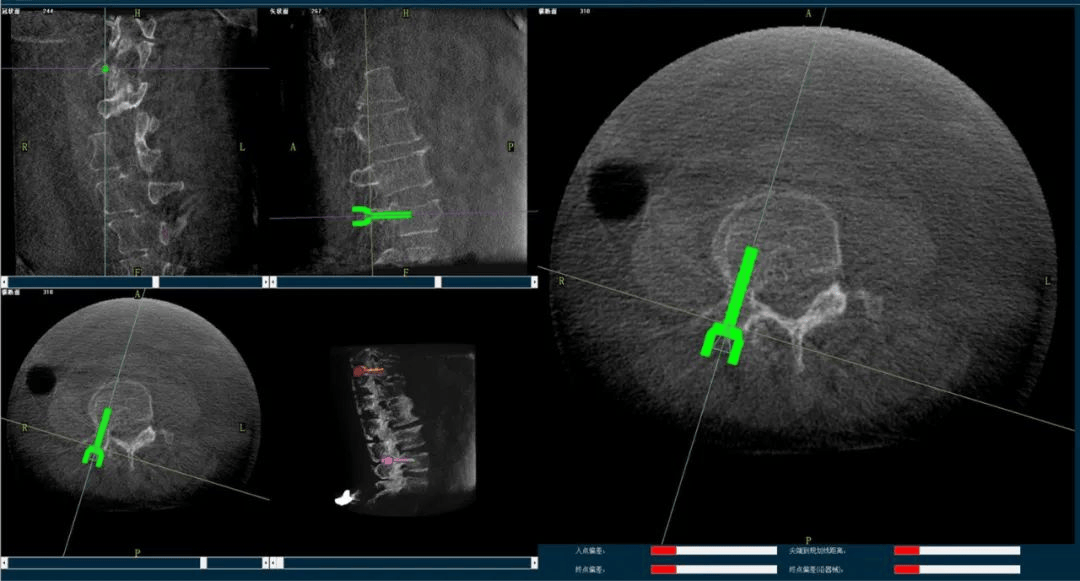

術(shù)中,手術(shù)團(tuán)隊(duì)先對患者進(jìn)行三維影像掃描,將圖像同步傳輸至機(jī)器人成像系統(tǒng)后,利用骨科手術(shù)機(jī)器人導(dǎo)航系統(tǒng)做好手術(shù)規(guī)劃,隨后利用其機(jī)械臂,將手術(shù)工具精確定位到“目的地”,鋪好“通道”,這就很好的解決了醫(yī)生“盲穿”的問題。